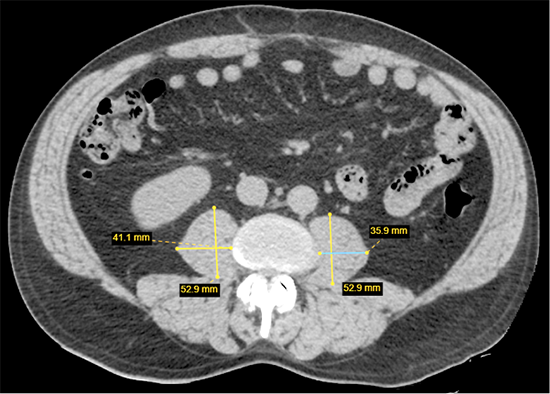

Patogiausias ir šiuo metu dažniausiai naudojamas tyrimas raumenų masei nustatyti yra KT. Ji gali būti laikoma „auksiniu standartu“ [26]. KT tyrimas gali tiksliai diferencijuoti raumeninį ir riebalinį audinį ir pateikti tikslią anatominę informaciją [26]. Šis dviejų audinių atskyrimas yra ypač reikšmingas vertinant riebalų depozitą raumenyse, žinomą kaip miosteatozė (angl. myosteatosis). Teoriškai, naudojant KT tyrimą, galima matuoti bet kurių kūno raumenų tūrį ir masę, tačiau šiandienos standartu laikoma Musculus psoas ploto matavimas L3 stuburo slankstelio lygmenyje [27] (2 pav.). Šio vieno raumens (o ne atskirų raumenų grupių ar bendro raumenų tūrio) matavimas yra patogus ir greitas būdas raumeniniam plotui vertinti, o mažas M. psoas raumens plotas yra patikimas neigiamas predikcinis veiksnys sergančiųjų onkologinėmis ligomis klinikinėms išeitims [27–29].

4a.png

2 pav. Musculus psoas ploto matavimas L3 stuburo slankstelio lygyje, atliekant KT